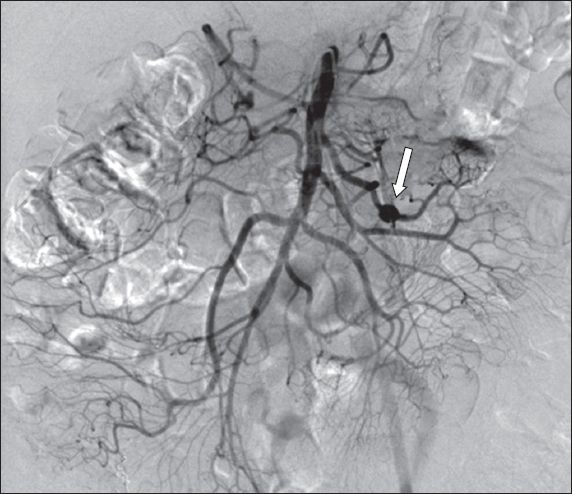

During the procedure, there was an incidental finding of a 9-mm fusiform jejunal artery aneurysm (

Fig. 1

Pre-embolisation CT mesenteric angiogram shows a 9-mm fusiform jejunal artery aneurysm (arrow).